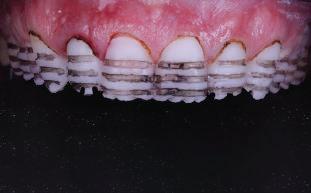

20 Dental Tribune Bulgarian Edition / октомври 2022 г. П ациентите със завършен растеж и скелетни проблеми обикновено представляват предизвикателство за ортодонт ската практика. Необходимостта от изваждане на зъби в комбинация с особеностите на възрастовата ортодонтия изисква особено внима ние. Фокусът върху критично важното значение на позицията на долните резци във връзка с дългосроч ната стабилност и постигането на оптимални оклузални взаимоотношения при затварянето на екстракционните пространства лесно може да излезе извън контрол. Когато към тези чисто кли нични проблеми се добави и стресът от натоваре ната практика, предизвикателството става още по-голямо. Всички тези фактори налагат използ ването на доказан подход с ясни и последовател ни стъпки, в което се разкрива силата на дисциплината „Алекзандър“ – предвидим протокол през целия процес на елиминиране на ротациите, ниве лиране на дъгите, затваряне на екстракционните пространства и финализиране на случая. Именно такъв е и случаят, който презентираме –екстракционен, скелетен клас 3 при възрастен па циент, лекуван по системата „Алекзандър“. ПРЕДВИДИМИ РЕЗУЛТАТИ ПРИ ПАЦИЕНТИ СЪС ЗАВЪРШЕН РАСТЕЖ И СКЕЛЕТЕН КЛАС 3, ИЗПОЛЗВАЙКИ ЕКСТРАКЦИОННО ЛЕЧЕНИЕ ПО ДИСЦИПЛИНАТА „АЛЕКЗАНДЪР“ Д-р Радой Димитров, България Преди започване на лечение клиничен случай | ортодонтия Фиг. 1а–1e Преди започване на лечение. Пациентът пристига в практиката с основното оплакване от невъзмож ност за нормално дъвчене. Снета е цялата необходима диагностична ин формация. Фиг. 1f–1h Снимки в профил и анфас. Фиг. 1i–1k Панорамна снимка, телерентгенография и анализ на телерент генография. Фиг. 1а Фиг. 1d Фиг. 1f Фиг. 1g Фиг. 1h Фиг. 1e Фиг. 1b Фиг. 1c Фиг. 1i Фиг. 1j Фиг. 1k

closed.

21Dental Tribune Bulgarian Edition / октомври 2022 г. ДИАГНОСТИЧНИ РЕЗУЛТАТИ: 1. Възраст на пациента: 21 години 2. Скелетен клас III (ANB 0) 3. Зъбен клас 3 4. Ръбцова захапка във фронта, кръстосана в дисталните участъци 5. Тясна горна челюст 6. Overjet – 0 мм, Overbite – 0 мм 7. Несъответствие на горната с долната средна линия 8. Единични контакти в ЦО 9. Хиподивергентен тип на растеж SN/MP – 33.5 10. Неравен гингивален контур 11. Неравна линия на усмивката 12. Тенденция за рецесии в долен фронт ПРЕПОРЪЧИТЕЛНО ЛЕЧЕНИЕ: Пълно ортодонтско лечение с метални брекети „Алекзандър“ Корекция на клас 3 захапката в областта на кучешките зъби с екстракция на първите пре молари в долна челюст Корекция на кръстосаната захапка в дистални участъци Коригиране на ръбцовата захапка във фронта Подобряване на ОJ и OB на пациента Стрипинг в долен фронт Подреждане на зъбите в горната и долната челюст Професионално хигиенизиране и профилактични дентални прегледи са препоръчителни на всеки 6 месеца. 1-ви месец След 1 месец са залепени брекети в горната челюст – поставена е еластична дъга. 016 NiTi. В долната челюст са елиминирани ротациите, поставена е стоманена дъга. 016SS, закалена с ток, и еластична верижка за затваряне на пространствата. 3-ти месец В долната челюст е поставена трета дъга – 17 x 25 NiTi с къси лигатури и верижка

В горната челюст се затварят пространствата с дъга .016SS и верижка. 5-и месец На 5-ия месец след залепяне на брекетите в долната челюст е поставена стоманена дъга 16 x 22 SS с четвъртито сечение, омега луп и тай бек. В горната челюст е поставена дъга 17 x 25 NiTi. Поради липсата на стабилни оклузални контакти са поставени лингвални верижки в областта на моларите, за да се предотврати нежелана ротация на 7-ите зъби. 6-и месец На 6-ия месец от началото на лечението са екстрахирани долните първи премолари, поставена е дъга 16 x 22 SS със затваряща чупка teardrop. Чупката се активира всеки месец по 1 мм с чинч-бек. клиничен случай | ортодонтия СТЪПКИ НА ЛЕЧЕНИЕТО Начало на лечението Лечението започва с поставяне на апарат за бърза експанзия в горната челюст. През първия месец от лечението са направени 24 оборота на апарата за експанзия. Залепени са брекети в долната челюст, поставена е дъга 17x25 CuNiTi, като са предпи сани клас 3 ластици (1/4”,4 1/2 oz) по време на сън, за да се осигури контрол върху торка на долните резци. Фиг. 2а Фиг. 3a Фиг. 4a Фиг. 3b Фиг. 4b Фиг. 3c Фиг. 4c Фиг. 3d Фиг. 4d Фиг. 3e Фиг. 4e Фиг. 5a Фиг. 5b Фиг. 5c Фиг. 5d Фиг. 5e Фиг. 6a Фиг. 6b Фиг. 6c Фиг. 6d Фиг. 6e Фиг. 7a Фиг. 7b Фиг. 7c Фиг. 7d Фиг. 7e Фиг. 2b Фиг. 2c Фиг. 2d

Dental Tribune Bulgarian Edition / октомври 2022 г.22 клиничен случай | ортодонтия 14-и месец В горната и долната челюст са поставени последни стоманени дъга с омега луп и тай бек – 17 x 25 SS с четвъртито сечение. Назначени е ластик за средната линия в комбинация с клас 3 ластик (1/4”, 6 1/2 oz). Контролни рентгенографии 13-и месец Екстракционните пространства са затворени. Направена е контролна панорамна снимка за оценка позицията на корените. Взето е решение за презалепване на брекетите на 12, 22 и пръстените на 36 и 46. 21-ви месец Средната линия в горната и долната челюст съвпадат. Ластиците са спрени. Свалени са пръстените и брекетите в горната и долната челюст, зигзаг ластици не са използвани поради благоприятните оклузални взаимоотношения. Фиг. 11j Ортопантомография в края на лечението. Фиг. 11k Телерентгенография след края на лечението. Фиг. 11l Анализ на телерентгенографията след лечението. Фиг. 11m Последователност на дъгите в горната и долната челюст Фиг. 11n Суперимпозиция на PreOp и PostOp ортопантомографии. 10-и месец Затварянето на пространствата е предвидимо и контролирано, без да се отварят пространства в зъбната дъга. Фиг. 8a Фиг. 8b Фиг. 8c Фиг. 8d Фиг. 8e Фиг. 10a Фиг. 10b Фиг. 10c Фиг. 10d Фиг. 10e Фиг. 9a Фиг. 9b Фиг. 9c Фиг. 9d Фиг. 9e Фиг. 9f Фиг. 11a Фиг. 11f Фиг. 11j Фиг. 11l Фиг. 11m Фиг. 11n Фиг. 11k Фиг. 11g Фиг. 11h Фиг. 11i Фиг. 11b Фиг. 11c Фиг. 11d Фиг. 11e

Dental Tribune Bulgarian Edition / октомври 2022 г. 23клиничен случай | ортодонтия реклама Лечението е продължило 21 месеца. Проведено е домашно избелване с индивидуални шини. За автора: Д-р Радой Димитров завършва с отличие Факултета по дентална медицина към МУ–София през 2015 г. В продължение на 5 години работи в няколко водещи практики в София, като през 2019 г. заедно със своята съпру га д-р Траяна Димитрова основават собствена практика в гр. Гоце Делчев –Dimitrovi Dental Care. Посещава редица курсове за повишаване на квалификаци ята, но най-сериозен тласък в развитието на ортодонтската си практика получава след завършването на комплексната ортодонтска програма, воде на от д-р Иван Горялов, базирана на дисциплината „Алекзандър“ – система с повече от 50 години опит в целия свят. Д-р Димитров е член на Българския изследователски клуб „Алекзандър“. Взе ма участие като гост-лектор в симпозиума с международно участие The Power of the Alexander Discipline, който се проведе на 14–15.05.2022 г. С д-р Ди митров можете да свържете на тел. +359885 252 025. Заключение Представеният случай е ярък пример за възможностите и красо тата на дисциплината „Алекзандър“ – приложен е утвърден под ход с ясни правила и са постигнати очакваните цели. Резулта тът ще бъде дългосрочно стабилен, тъй като са спазени всички правила, които се отнасят към максимално комфортната пози ция на зъбите в края на лечението. Постигнати са красива усмив ка и стабилна оклузия. ПОСТИГНАТИ РЕЗУЛТАТИ ОТ ЛЕЧЕНИЕТО 1. Коригирана ръбцова захапка 2. Коригирана клас 3 захапка в областта на ку чешките зъби 3. Коригирана кръстосана захапка в дисталните участъци 4. Коригиран овърджет и овърбайт 5. Разширена е горната зъбна дъга 6. Подредени зъби в горната и долната челюст 7. Постигната е стабилна захапка с множество контакти в ЦО 8. Драматично е подобрена дъвкателната функ ция 9. Подобрена е линията на усмивката ДРУГИ ПРОВЕДЕНИ ДЕНТАЛНИ ПРОЦЕДУРИ 1. Домашно избелване на зъбите 2. Екстракция на мъдреците Фиг. 12a Фиг. 12b Фиг. 12c Фиг. 12eФиг. 12d Фиг. 12f Фиг. 12g Информация за дати, цени и отстъпки www.bracescourses.com 0889 22 55 01 Практически курсове лектор д-р Иван Горялов Дисциплината „Алекзандър“ ПЪТЯТ КЪМ СУПЕРУСМИВКИТЕ 100% връщане на цялата сума, ако не сте удовлетворени след преминаване на Ниво 1 Директно и индиректно залепяне на брекети Анализ, диагноза и план на лечение Лечение на клас 2 дълбока захапка Екстракционно лечение Лечение на клас 3 отворена захапка НИВО 5НИВО 1 НИВО 2 НИВО 3 НИВО 4